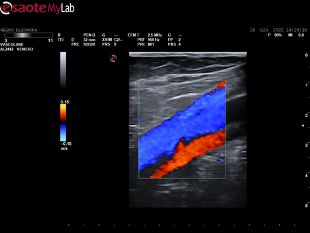

Svolgo attività quotidiana di diagnostica vascolare non invasiva, di cura delle arteriopatie e di tutte le patologie venose: varici, trombosi venose profonde acute, sindrome post-trombotica, ulcere venose e/o linfatiche, edemi degli arti inferiori, ulcere croniche.

• Ecocolordoppler vascolare

120 €